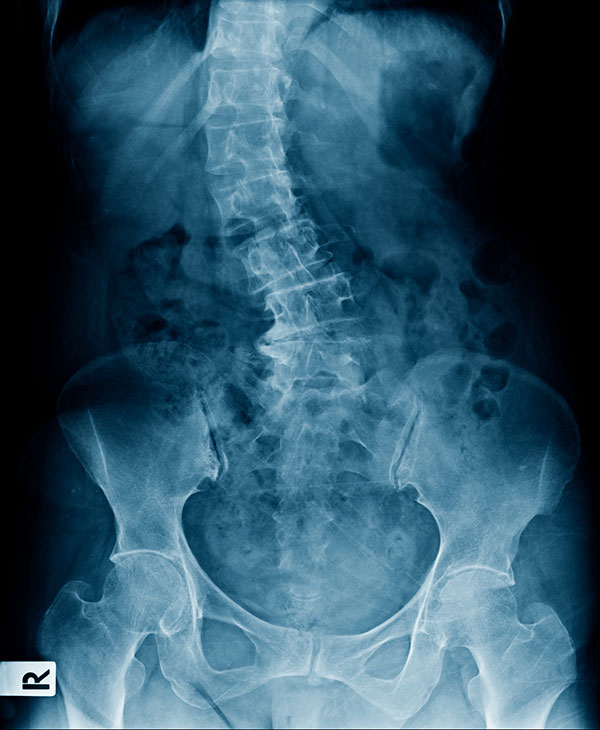

レントゲン検査、装具や手術の判断などについては、必ず医師の診断が必要です。

成人の側弯症は背骨の歪み、肋骨の歪み、骨盤の歪み、筋肉のアンバランス、可動域の制限、神経の圧迫などによって、このような様々な悩みを抱えています。

「思春期特発性側弯症の残存」や「変性側弯症」など大人の側弯症の殆どは、「構築性側弯」と分類されて、不可逆的な骨の変形があるため、完全にまっすぐな背骨に戻すことは困難となります。

Q11レントゲン画像は持参した方がよいですか?

お持ちの場合は、レントゲン画像やその写真をご持参ください。

病院で測定されたコブ角も分かれば参考になります。

初診時にレントゲンのデータをお持ちの方はご持参ください。

コブ角の角度が分かるようでしたらお知らせください。